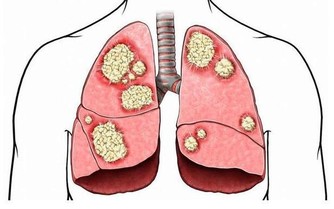

呼吸增快主要見於肺炎、肺栓塞、胸膜炎、支氣管哮喘、充血性心力衰竭、代謝亢進以及神經精神障礙等。